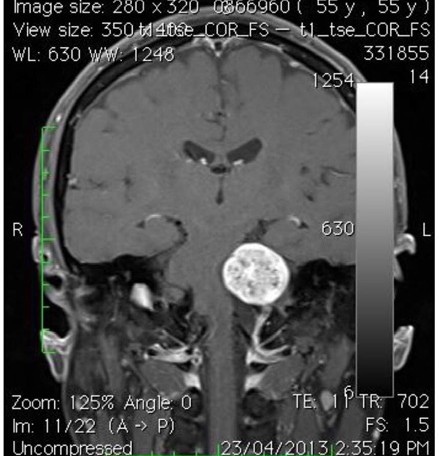

聽覺神經瘤(Acoustic Neuroma)又稱為聽神經許旺氏細胞瘤(Schwannoma),或前庭神經鞘瘤(Vestibular Schwannoma),是許旺氏細胞瘤沿第8條腦神經線生長所致。聽覺神經瘤佔了所有顱內腫瘤(Brain Tumour)總數約8%。不過在區域性劃分上,聽覺神經瘤在小腦腦橋角(Cerebral - pontine Angle)是常見的腫瘤,大約佔了所有小腦腦橋角區域腫瘤(Cerebral-pontine Angle Tumor)的80至90%。